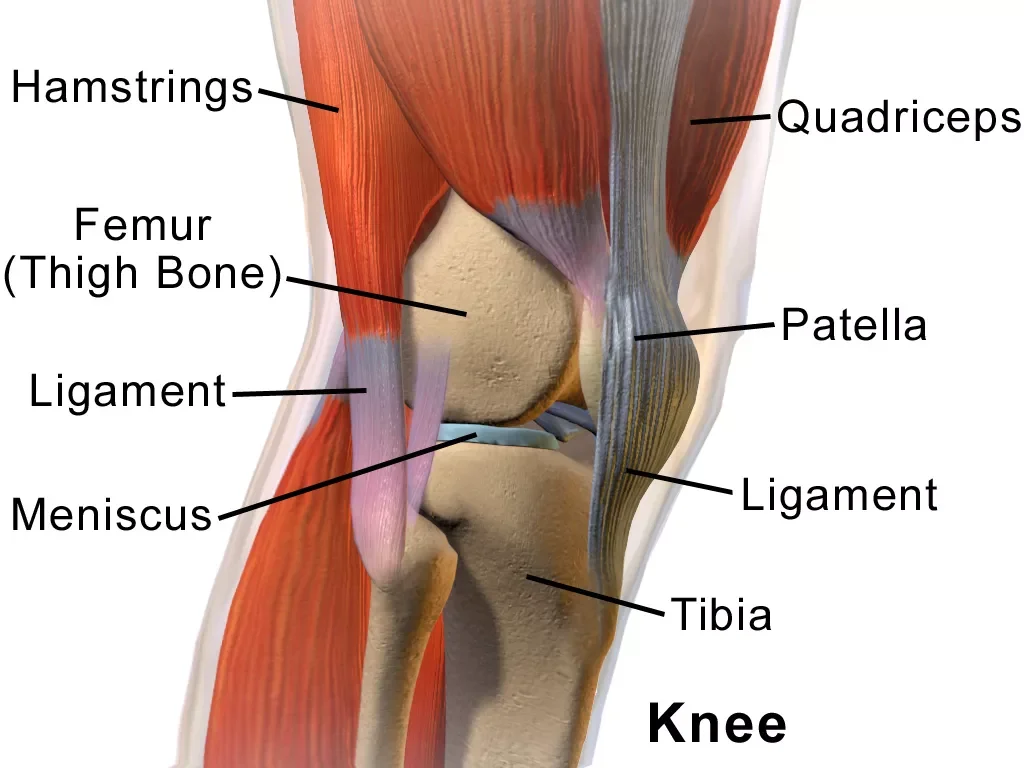

Koleno

Strokovno o operacijah, rehabilitaciji in zdravljenju poškodb in bolezni kolena. Artroskopija, endoproteza, rekonstrukcija križnih vezi in več.